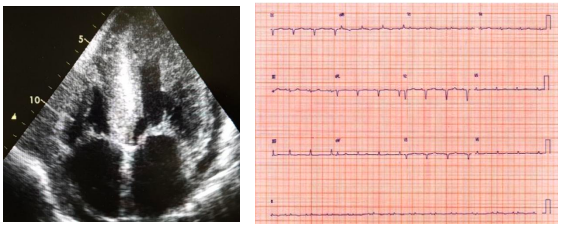

Mulher de 53 anos com quadro de dispneia aos mínimos esforços, hepatomegalia, ascite e

edema de membros inferiores há 5 meses. Nega história familiar de cardiopatia. Realizou o

ecocardiograma e o eletrocardiograma a seguir:

Considerando essas informações, a hipótese diagnóstica mais provável é